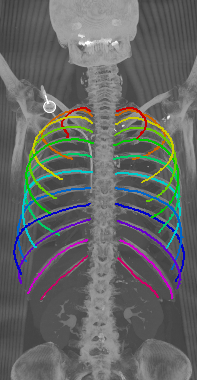

Refer to caption

Figure 5: Automatically generated centerline splines associated with the FCNN outputs displayed in Figure 4. The selected case above display common difficulties which are inherent in the data set, such as pads (a) or cables (b), internal devices such as pacemakers (c), stents (d), spinal (e) and femural/humeral implants (f), injected contrast agents (g), patient shape variations such as scoliosis (h), limited field of views (FOVs), i.e. partly missing first (i) or twelfth rib (j).

With an average Euclidean distance error of 0.787 mm, we obtained an overall result that is generally better compared to what is reported in the state of the art. Although, it needs to be kept in mind that results are unfortunately not directly comparable as both the data sets as well the evaluation metrics significantly differ across prior work. Similarly to the results obtained on the probability maps, distance errors are significantly higher for first and twelfth rib compared to the rest of the rib cage. As discussed, this is caused by the intrinsic challenges of these ribs, but certainly also an affect of error propagation in that sense that the quality of the probability maps also impacts centerline extraction. Interestingly, the right ribs are generally slightly worse compared to the left ribs, probably due to a slightly unbalanced data set with more challenges on the right side. Figure 5 shows the centerlines which were automatically generated using our walker algorithm from the corresponding network outputs displayed in Figure 4.